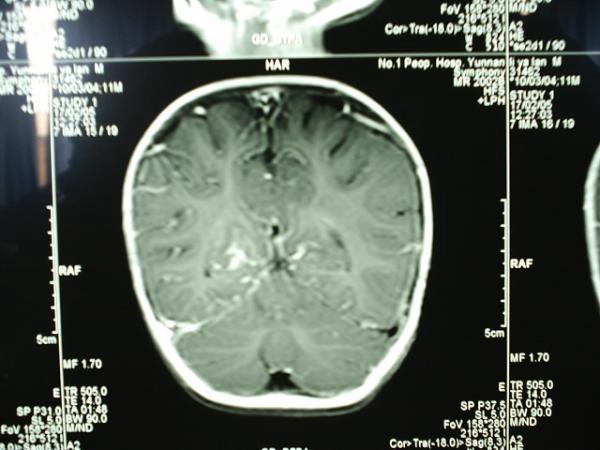

小儿结核性脑膜炎合并脱髓鞘改变MRI

病变部位在右侧大脑半球胼胝体压部强化部分。大家注意看